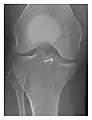

a

b

c

Figure 1: A 56-year-old woman presenting with left knee pain after a fall. (a) Initial anteroposterior radiograph was considered normal, however, subtle cortical disruption of the anterior rim of the medial tibial plateau, medial to the tibial spine, is noted (arrow). (b) Coronal T1-weighted MRI confirms the cortical disruption (arrow) and shows extensive fracture through the proximal tibia. (c) Coronal proton density-weighted image with fat saturation shows extensive edema in the subchondral bone. Note also hypersignal adjacent to the medial collateral ligament corresponding to a grade I sprain (arrowheads).[1]